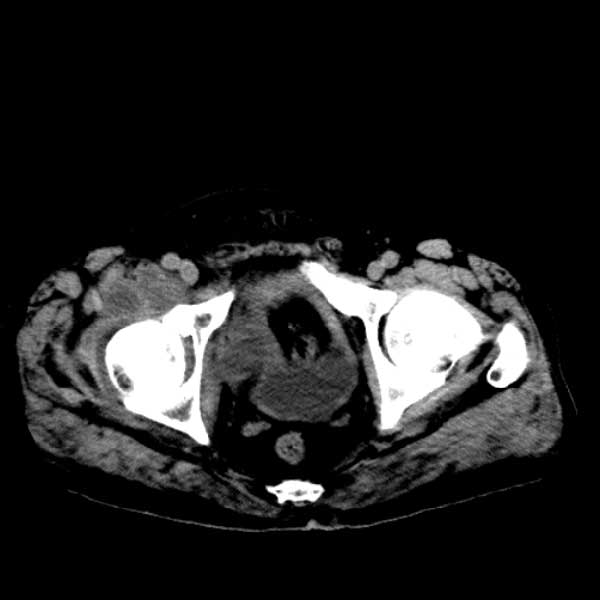

标题: CT13513:男 71 腹部疼痛20余天,近几天高热就诊,骨窗未见异 [打印本页]

标题: CT13513:男 71 腹部疼痛20余天,近几天高热就诊,骨窗未见异

考虑感染性病变可能性大,起源于阑尾?

感染,脓肿形成

考虑为化脓性阑尾炎.脓肿形成.及多肌肉累及.

考虑右侧腰大肌脓肿,向右髂窝、右腹股沟流注。

支持化脓性阑尾炎伴右髂窝脓肿、腰大肌腰方肌脓肿形成。

考虑腹腔及盆腔化脓性炎症,累及右侧髋关节及腹股沟区.

首先考虑化脓性阑尾炎伴腰大肌、腰方肌脓肿,不除外回盲部结核。

回盲部癌待排除。

患者肠镜检查考虑结肠癌,病理证实

患者肠镜检查考虑结肠癌,病理证实。肺部ct可见多发结节,考虑转移